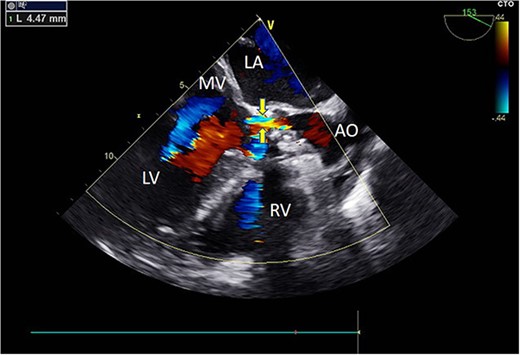

Intraoperatively, after self-expanding the aortic valve, TEE monitoring confirmed excellent cardiac function, disappearance of aortic valve regurgitation, secure anchoring of the aortic valve prosthesis, and no obstruction to the mitral valve leaflets or coronary ostia. The aortic valve velocity and pressure gradient upstream of the valve decreased compared to preoperative values, with a maximum velocity of 166 cm/s and a pressure gradient of 11 mmHg (Fig. 3). However, a periprosthetic leak with a residual width of ~4.5 mm was observed at the self-expanding valve’s interface with the native annulus (Fig. 4). Based on preoperative data, the decision was made to re-expand and reshape the prosthesis. Postdilation, TEE monitoring showed a reduction in the periprosthetic leak to 1.5 mm (Fig. 5), a significant improvement compared to predilation. Following satisfactory self-expansion results, the planned percutaneous ASD closure procedure was performed under ultrasound guidance. The closure device was securely positioned in the atrial septum, and TEE examination showed no deformation or impingement of the self-expanding valve (Fig. 6). Atrial shunting was eliminated, and the outcome exceeded expectations.

Intraoperative TEE: Long-axis aortic view displays a 4.5 mm-wide perivalvular blood flow bundle around the aortic valve (arrow). Abbreviations: LA - left atrium; LV - left ventricle; RV - right ventricle; AO - aortic.